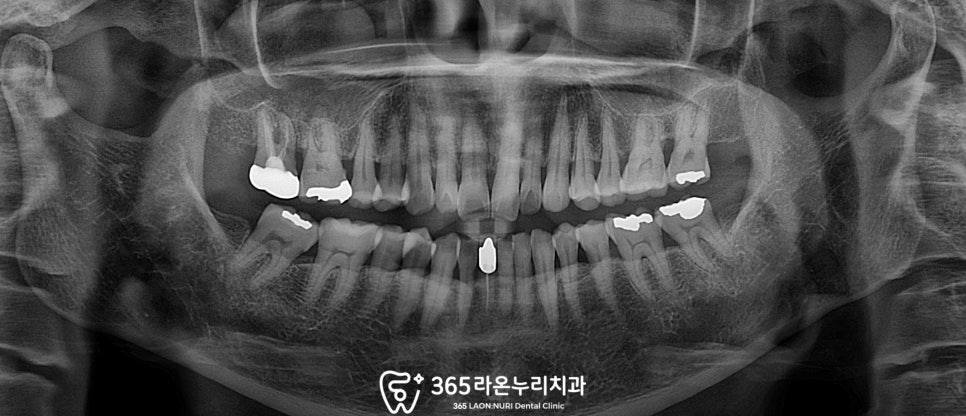

먼저 오산 치과 에서 확인한

엑스레이와 구강 사진입니다.

옛날에 수복해둔 아말감과

골드로 만든 보철물이 있고,

도드라지게 보이는 문제점은 없었습니다.

통증을 호소하는 부분은 오른쪽 위 부분이었는데,

골드인레이로 수복했던

상악 우측 제1대구치(#16)가 의심스러웠습니다.